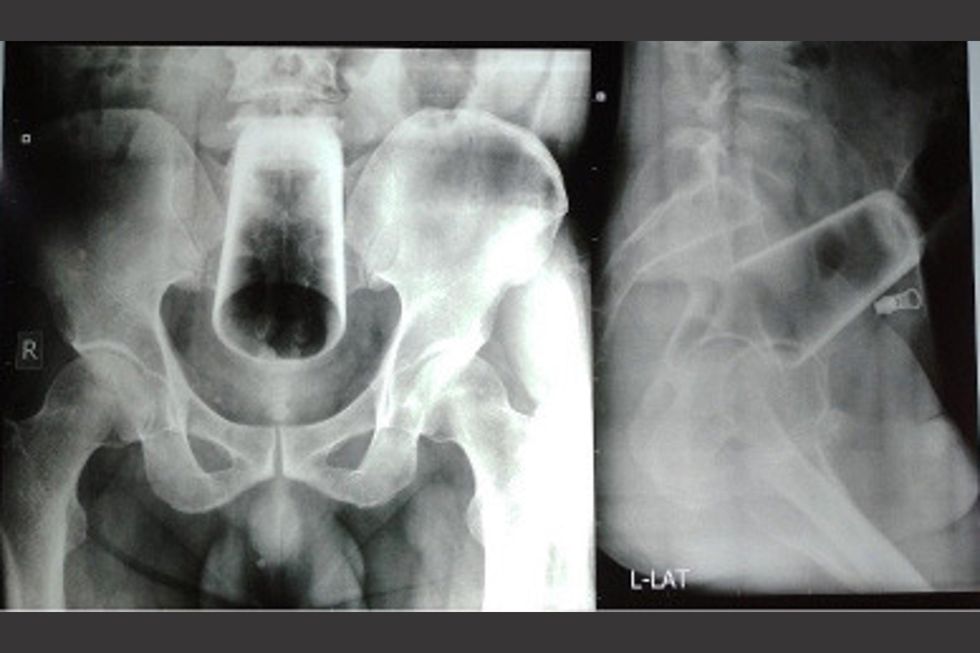

According to the Journal of Nepal Medical Centre, which published the case, the patient was taken for an X-ray which revealed the household object wedged deep into his rectum.